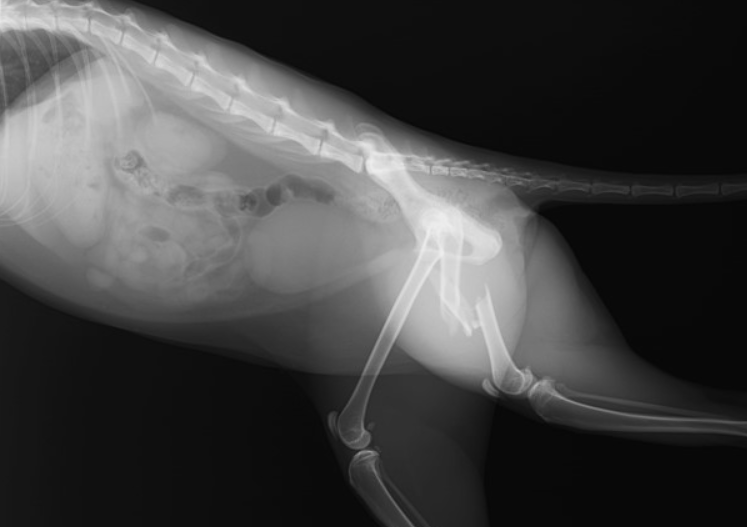

左大腿骨(後ろ足の骨)の粉砕骨折の事例です。外に出る子だったので、交通事故に遭われたのだと思います。

1. レントゲン検査:骨折の種類と場所を正確に確認するためにレントゲン検査が行われます。